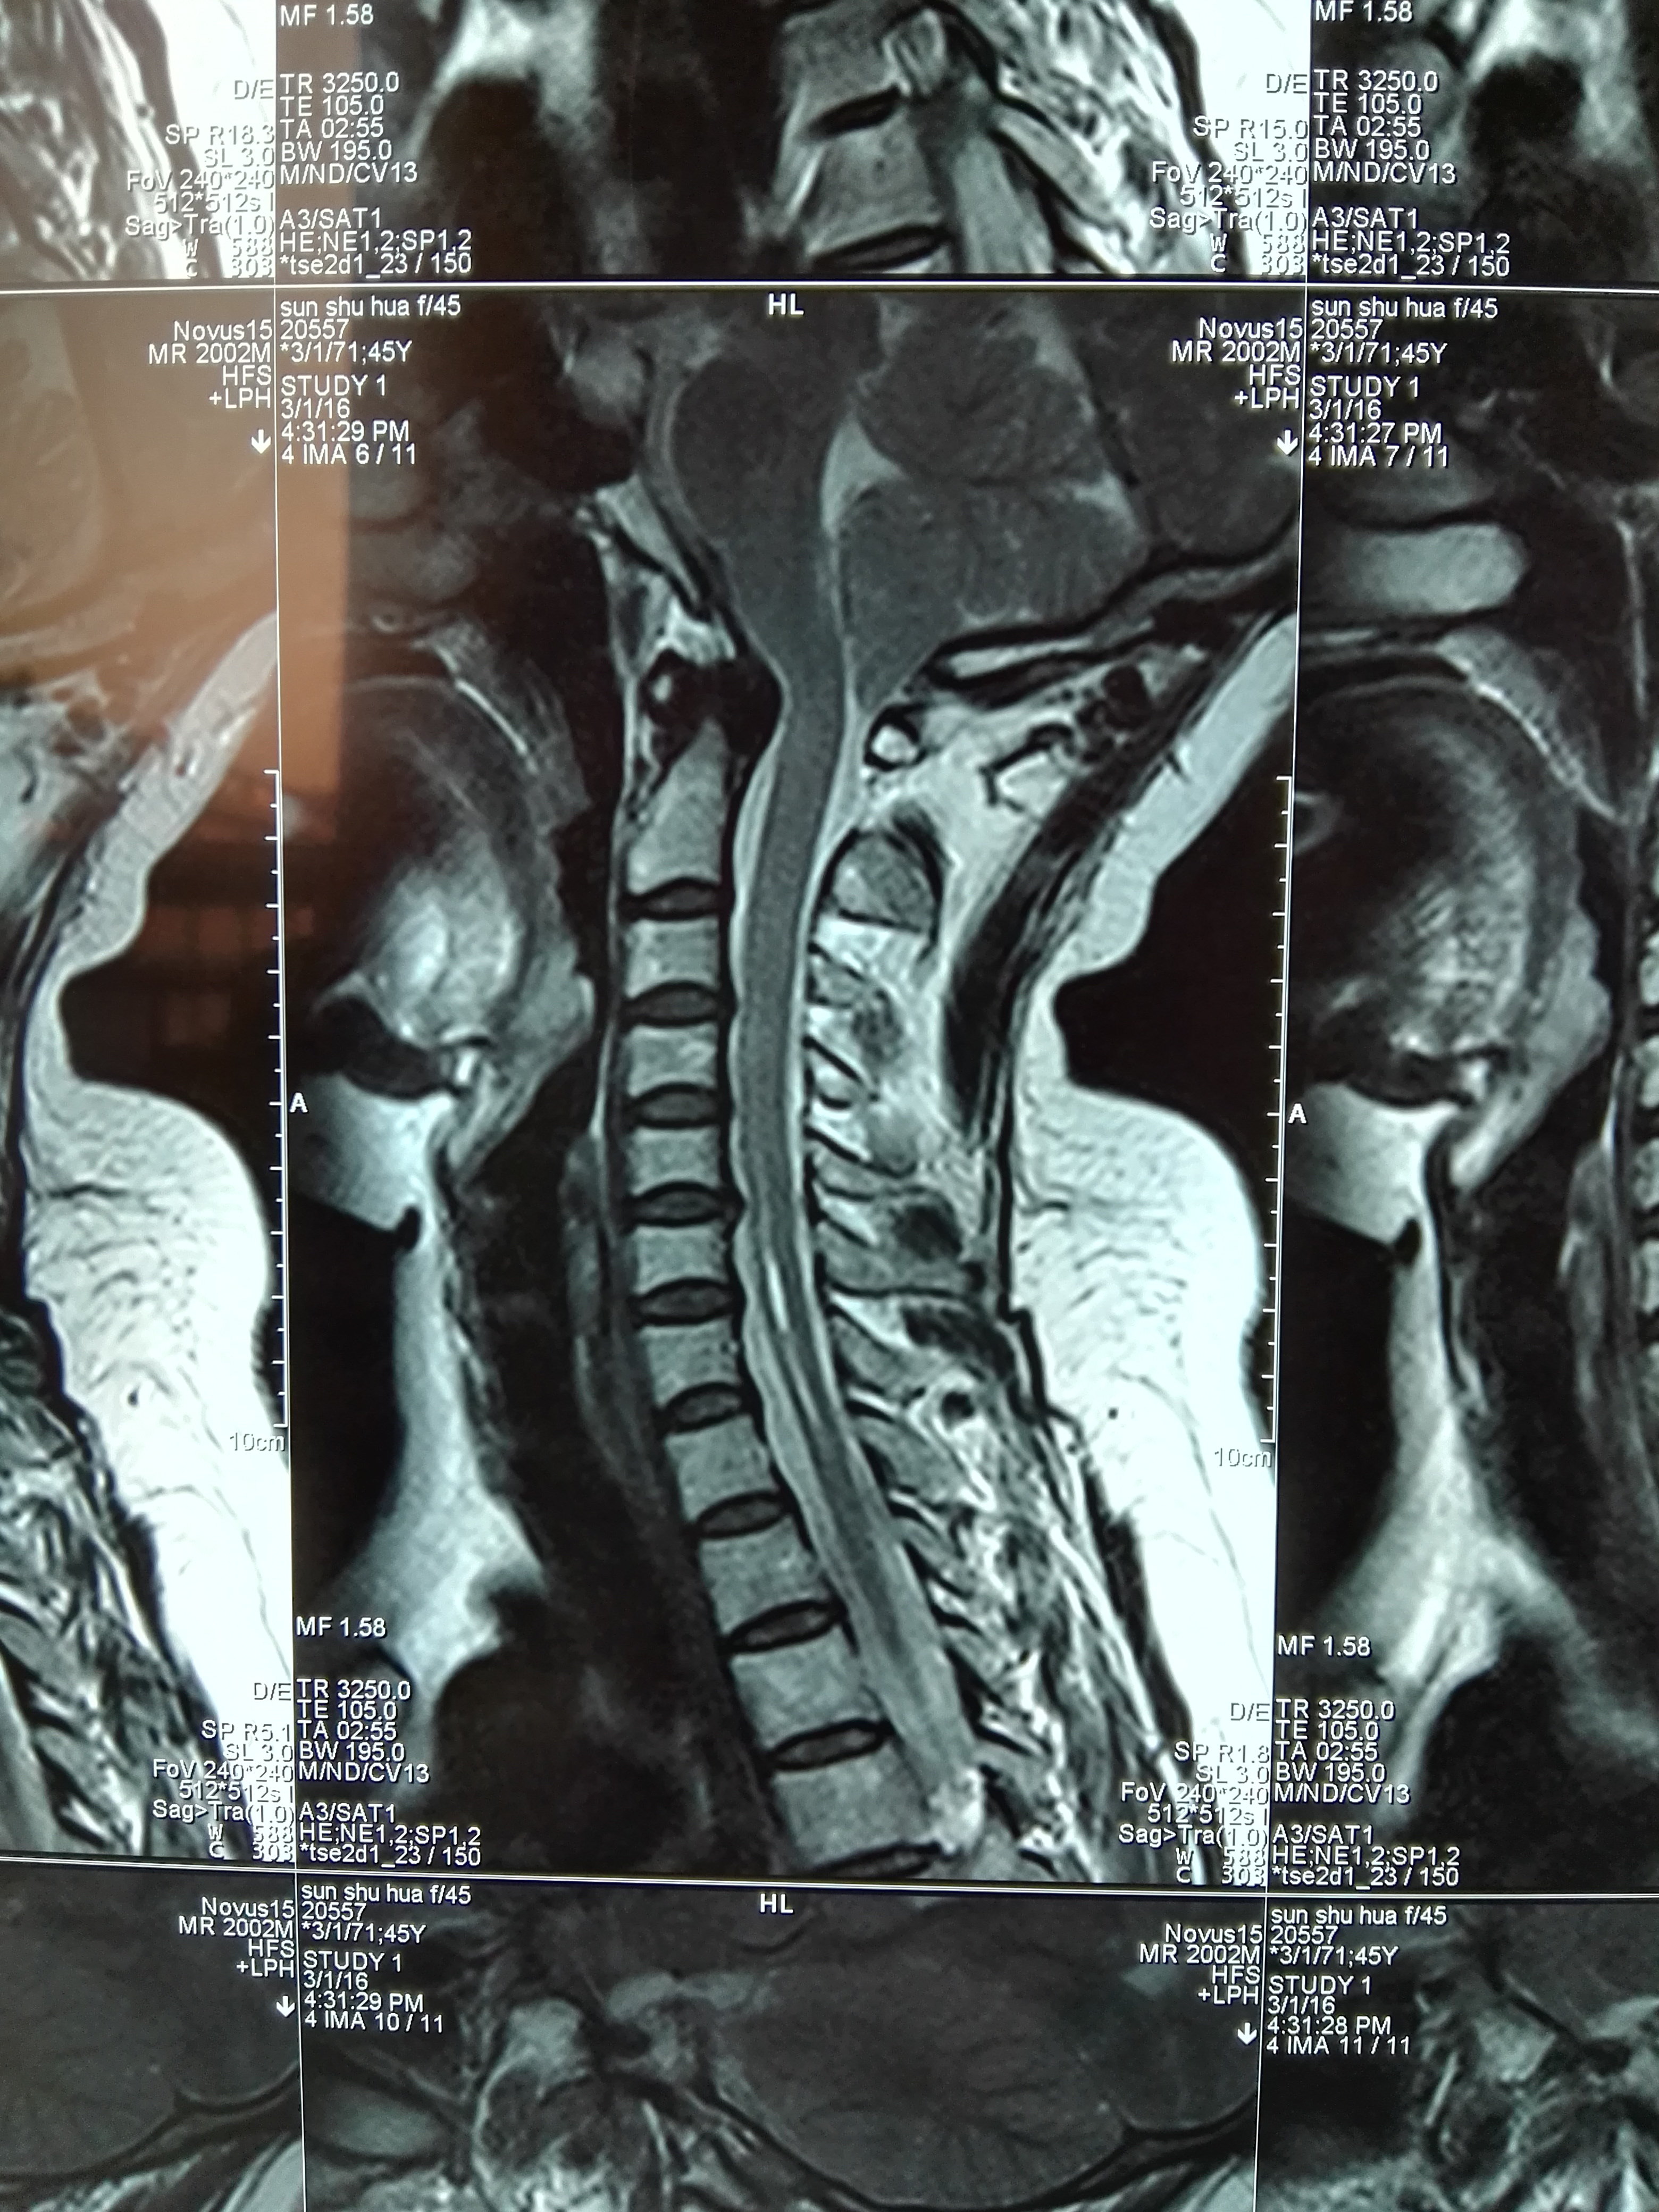

脊髓空洞症专业科普

图片尺寸3120x4160